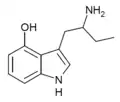

List of substituted α-alkyltryptamines

α-Alkyltryptamines are a group of substituted tryptamines which possess an alkyl group, such as a methyl or ethyl group, attached at the alpha carbon, and in most cases no substitution on the amine nitrogen.[17][18][19] α-Alkylation of tryptamine makes it much more metabolically stable and resistant to degradation by monoamine oxidase, resulting in increased potency and greatly lengthened half-life.[19] This is analogous to α-methylation of phenethylamine into amphetamine.[19]

Many α-alkyltryptamines are drugs, acting as monoamine releasing agents, non-selective serotonin receptor agonists, and/or monoamine oxidase inhibitors,[20][21][22][23] and produce psychostimulant, entactogen, and/or psychedelic effects.[17][18][19] The most well-known of these agents are α-methyltryptamine (αMT) and α-ethyltryptamine (αET), both of which were used clinically as antidepressants for a brief period of time in the past and are abused as recreational drugs.[18][19] In accordance with its action as a dual releasing agent of serotonin and dopamine, αET has been found to produce serotonergic neurotoxicity similarly to amphetamines like MDMA and PCA, and the same is also likely to hold true for other serotonin and dopamine-releasing α-alkyltryptamines such as αMT, 5-MeO-αMT, and various others.[24]

αMT | 1-(1H-Indol-3-yl)propan-2-amine | 299-26-3 |

4-HO-αMT | 3-(2-aminopropyl)-1H-indol-4-ol | 15066-09-8 |